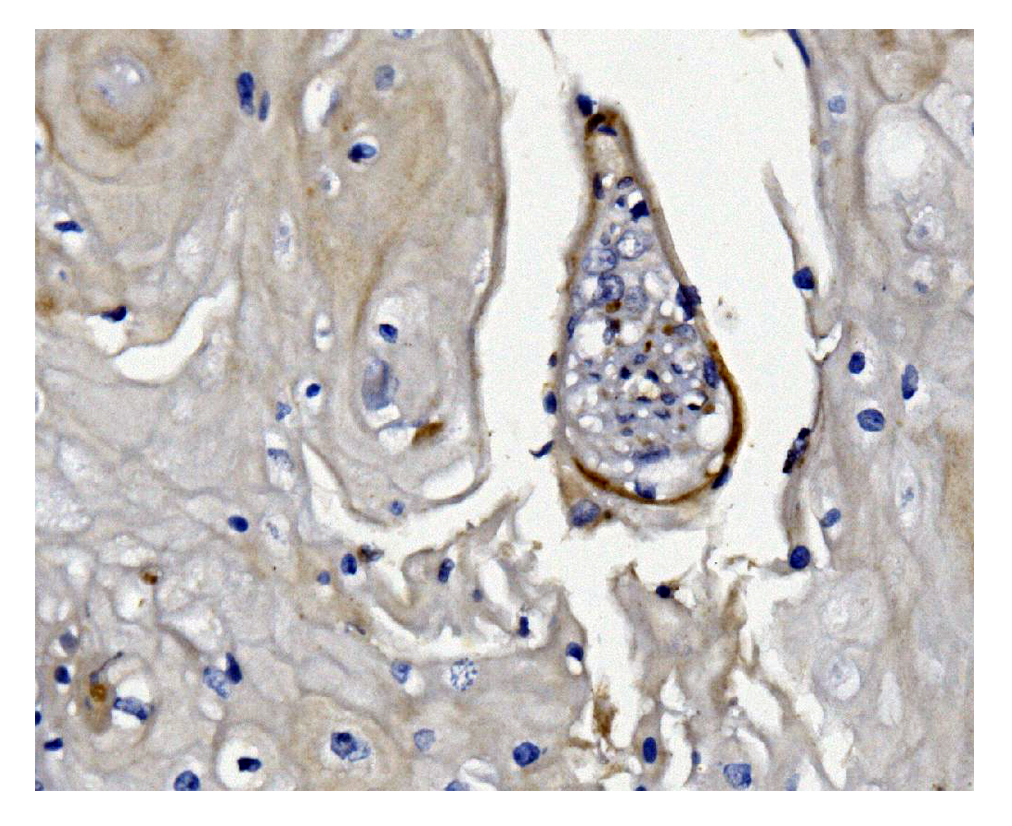

IHC analysis of GSDMD using anti-GSDMD antibody (M02842-1).

GSDMD was detected in a paraffin-embedded section of human esophagus tissue. Biotinylated goat anti-mouse IgG was used as secondary antibody. The tissue section was incubated with mouse anti-GSDMD Antibody (M02842-1) at a dilution of 1:200 and developed using Strepavidin-Biotin-Complex (SABC) (Catalog # SA1021) with DAB (Catalog # AR1027) as the chromogen.